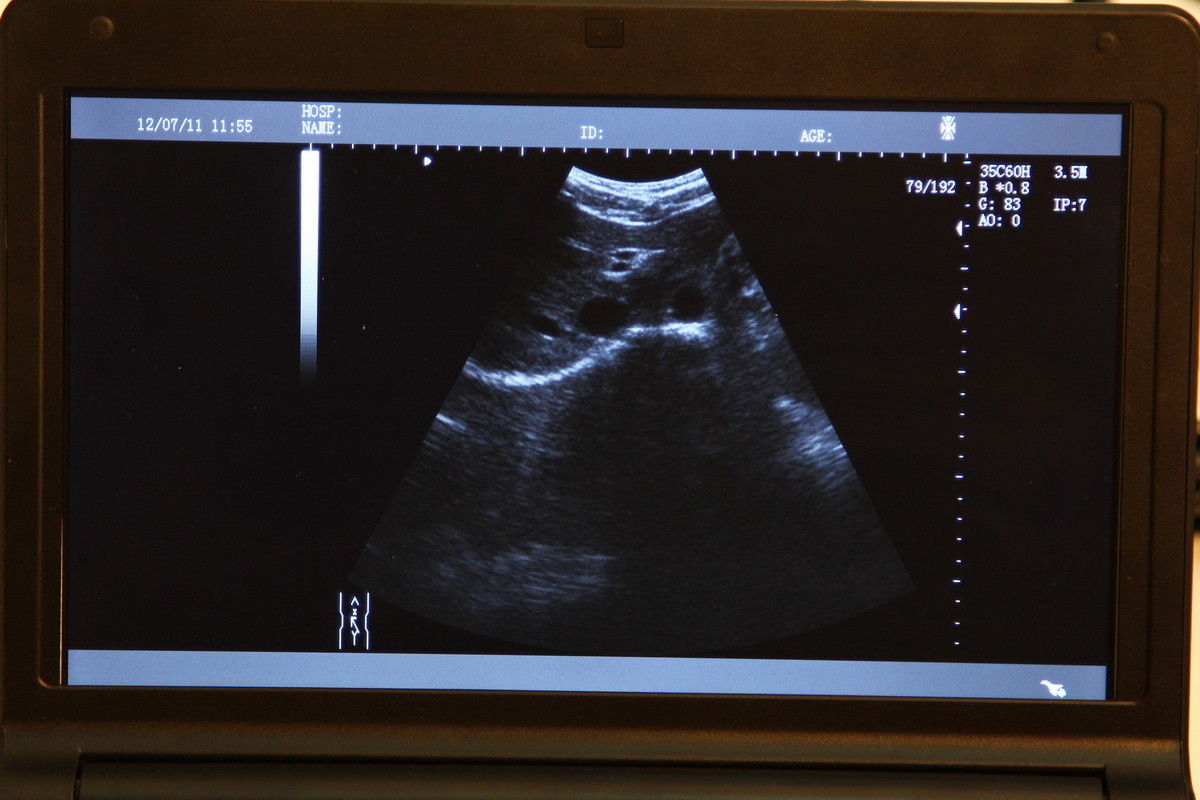

Veterinary vet Digital Laptop Ultrasound Scanner w Rectal Linear Probe 3D A+ 190891459831

Veterinary vet Full Digital Laptop Ultrasound Scanner 5.0 Rectal Probe 3D Sale 190891462251

Veterinary vet Full Digital Laptop Ultrasound Scanner Micro-Convex Probe 3D Sale 190891712110

Veterinary vet Full Digital Laptop Ultrasound Scanner Micro-Convex Probe Free 3D 190891712110

Veterinary VET Laptop Ultrasound Scanner Machine Rectal Linear Probe +3D Animals 190891052124

Veterinary VET Laptop Ultrasound Scanner System Rectal Linear Probe +3D Software 190891052124

Veterinary Vet Portable Digital Ultrasound Scanner Machine Micro-Convex Probe 3D 190891711977

Veterinary Vet SVGA Digital Ultrasound Scanner +Micro-Convex Probe 3D Software 190891975430

Veterinary Wifi Wireless Portable Ultrasound Scanner Convex Array Probe 3.5Mhz

Veterinary WIRELESS Ultrasound Scanner Machine Handheld Micro Convex Probe